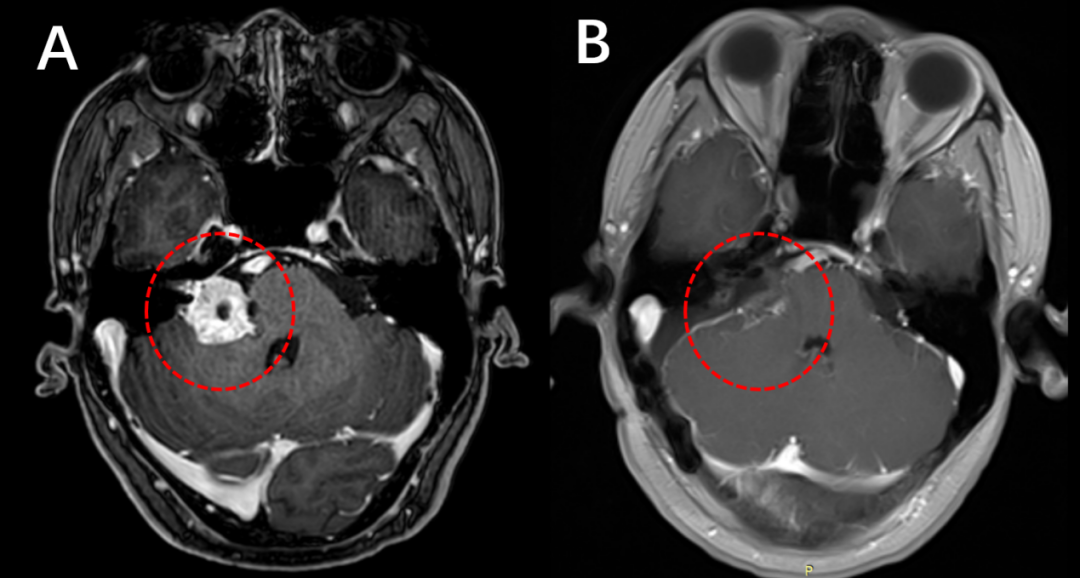

术前(左)和术后(右)增强磁共振检查,对比提示肿瘤完全切除(红色圈内的肿瘤消失)